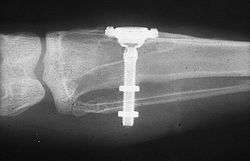

The early part of the 20th century saw a number of implants made of a variety of materials. One of the earliest successful implants was the Greenfield implant system of 1913 (also known as the Greenfield crib or basket).[47] Greenfield's implant, an iridioplatinum implant attached to a gold crown, showed evidence of osseointegration and lasted for a number of years.[47] The first use of titanium as an implantable material was by Bothe, Beaton and Davenport in 1940, who observed how close the bone grew to titanium screws, and the difficulty they had in extracting them.[48] Bothe et al. were the first researchers to describe what would later be called osseointegration (a name that would be marketed later on by Per-Ingvar Brånemark). In 1951, Gottlieb Leventhal implanted titanium rods in rabbits.[49] Leventhal's positive results led him to believe that titanium represented the ideal metal for surgery.[49]

In the 1950s research was being conducted at Cambridge University in England on blood flow in living organisms. These workers devised a method of constructing a chamber of titanium which was then embedded into the soft tissue of the ears of rabbits. In 1952 the Swedish orthopaedic surgeon, Per-Ingvar Brånemark, was interested in studying bone healing and regeneration. During his research time at Lund University he adopted the Cambridge designed "rabbit ear chamber" for use in the rabbit femur. Following the study, he attempted to retrieve these expensive chambers from the rabbits and found that he was unable to remove them. Brånemark observed that bone had grown into such close proximity with the titanium that it effectively adhered to the metal. Brånemark carried out further studies into this phenomenon, using both animal and human subjects, which all confirmed this unique property of titanium. Leonard Linkow, in the 1950s, was one of the first to insert titanium and other metal implants into the bones of the jaw. Artificial teeth were then attached to these pieces of metal.[50] In 1965 Brånemark placed his first titanium dental implant into a human volunteer. He began working in the mouth as it was more accessible for continued observations and there was a high rate of missing teeth in the general population offered more subjects for widespread study. He termed the clinically observed adherence of bone with titanium as "osseointegration".[28](p626)